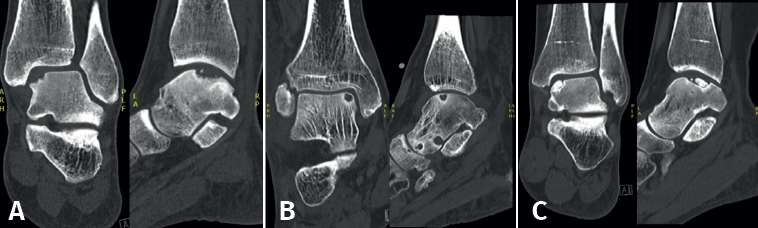

Lesions can be characterized by location, morphology, and size. Location can be described using a 9-grid anatomical scheme of the talus, as described by Raikin et al., shown in Figure 1(14). The morphology of OLTs can be described as crater-like, cystic, or fragmentary (Figure 2)(4,15,16). Lesion size should be reported in anterior-posterior plane, medial-lateral plane, and depth, allowing for calculation of lesion surface area and volume(4). However, there is no consensus on the reporting on morphology of OLTs, and while radiological classification systems for OLTs exist, they lack validation and utilize inconsistent terminology. Moreover, lesion size measurement methods vary, further contributing to inconsistency in lesion characterization in literature(15).

As an additional procedure, the debrided cyst can be filled with cancellous bone, particularly for large lesions, since the insufficient stem cells in the subchondral bone in these cases lead to a lower likelihood of adequate regeneration of damaged cartilage and subchondral bone(22,38). For primary OLTs, retrograde drilling has a success rate between 68% and 100% and a complication rate of 5%(22,29).

Fixation techniques have shown clinical and radiological success in 8 out of 10 patients, also maintaining their success in the long term (Figures 5 and 6). As these techniques preserve the hyaline cartilage and provide superior healing of the subchondral bone, they are advantageous over other surgical treatment options for OLTs, when feasible(39,41).